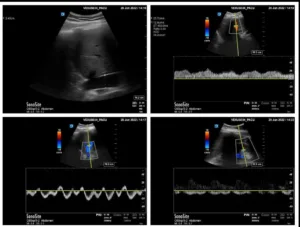

A 53 year old man with heart failure with reduced ejection fraction (~37%) secondary to non-ischemic cardiomyopathy and end-stage kidney disease (ESKD) recently initiated on hemodialysis underwent a right upper quadrant ultrasound for elevated liver function tests. Despite a radiology report indicating “normal liver morphology and hemodynamics,” a review of images by the nephrology team revealed severe venous congestion. This was evidenced by a dilated inferior vena cava (IVC) with an approximate anteroposterior diameter of 3 cm, systolic (S-wave) reversal in the hepatic vein flow, and a pulsatile portal vein with some flow reversal (Figure 1). These sonographic findings are consistent with VExUS grade 3 (Figure 2).

Figure 1. Radiology-performed scan images demonstrating a dilated inferior vena cava (approximately 3 cm), S-wave reversal on hepatic vein Doppler and a pulsatile portal vein (below-the-baseline blebs represent flow reversal).